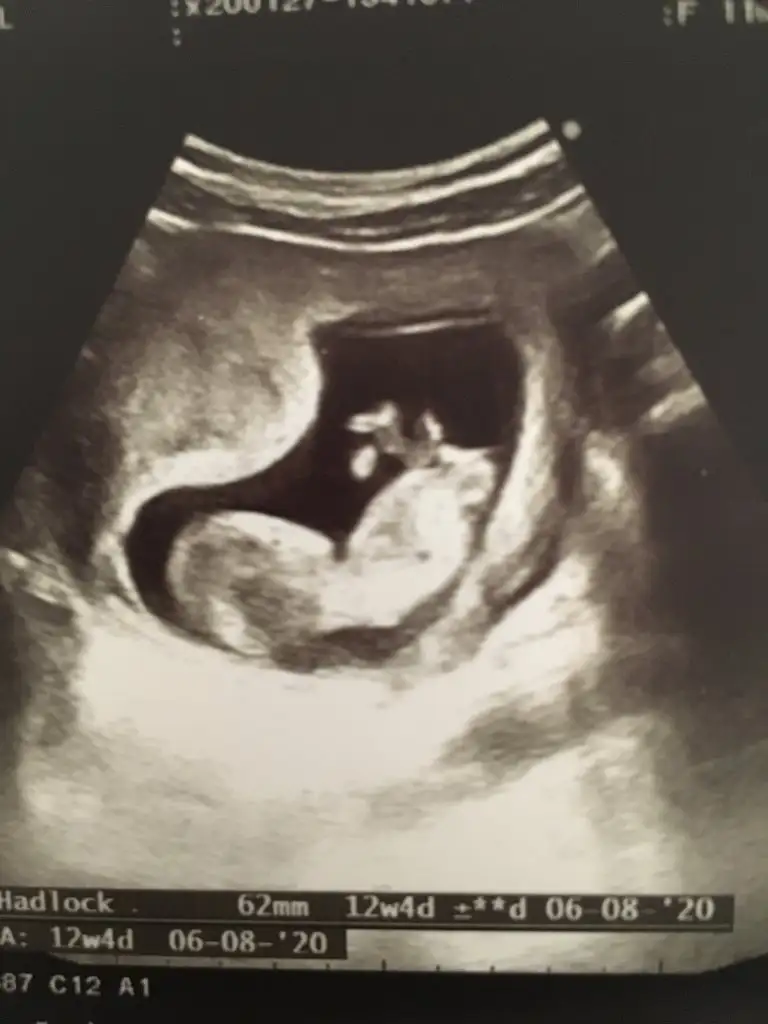

Gecen 12 haftalik istemistiniz bugun cekildik yine :) tahminde bulunabilir misiniz

20200203_163234.webp